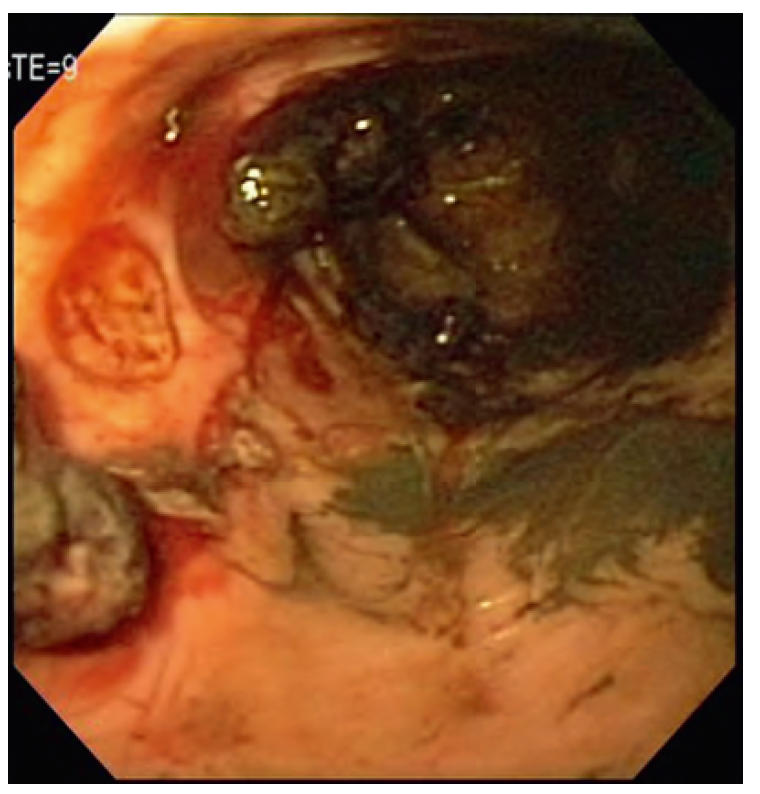

- 内镜是GUE最敏感的方法(图1),但胃内容物(大量血液及血块;图2)可掩盖病变。内镜可取材活检。溃疡边缘活检困难且价值有限,通常取溃疡基底及周围正常组织更易且信息量相当;慎取溃疡中心,极少致穿孔。若内镜活检致穿孔,该溃疡迟早也会自发穿孔。

图2. 胃内血块:内镜于角切迹向幽门观察,显示胃溃疡伴巨大血块。